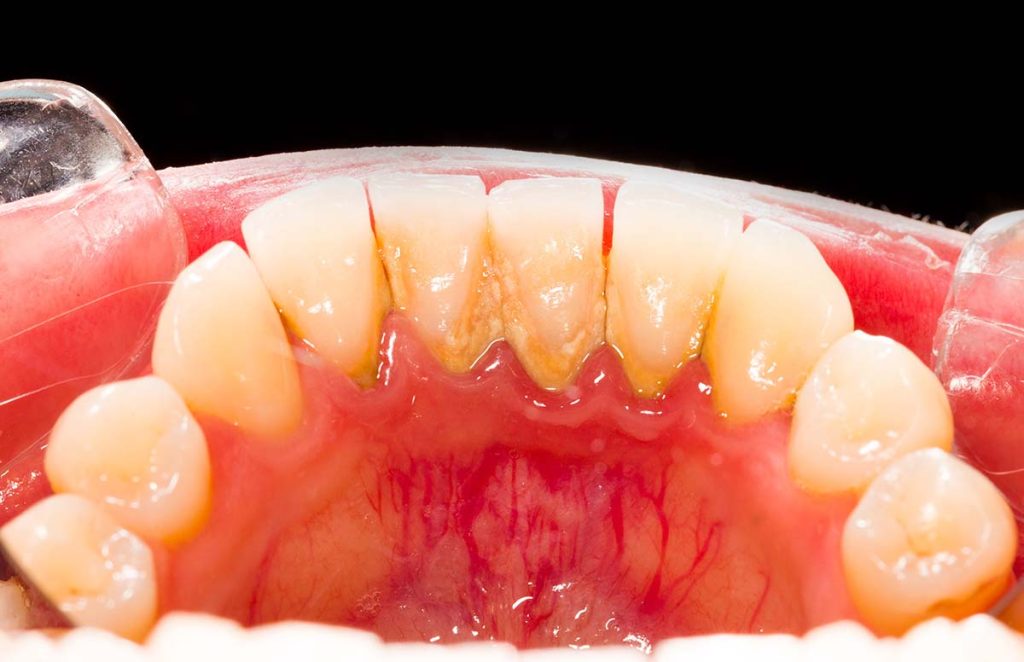

Tartar also referred to as dental calculus, is a rough plague that has hardened on the teeth. So, is tartar the same as plaque? Tartar is plaque that has not been removed or washed out for a long time. Tartar might also accumulate beneath the gum line and may irritate the gum tissues. Tartar offers […]